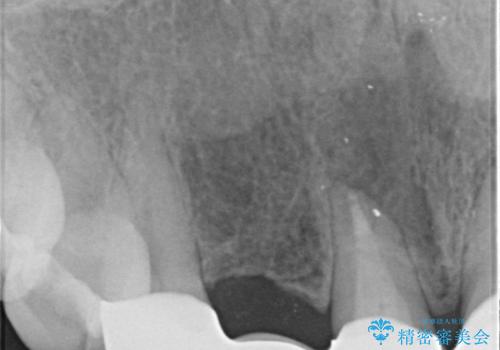

- 入れ歯での生活がストレスで他のものに変えたいとのことで来院された患者様です。

根の状態も良くなかったため、根管治療から行うこととなりました。

左上2番の歯は歯根が割れていたため抜歯し、入れ歯をブリッジに変えていきます。